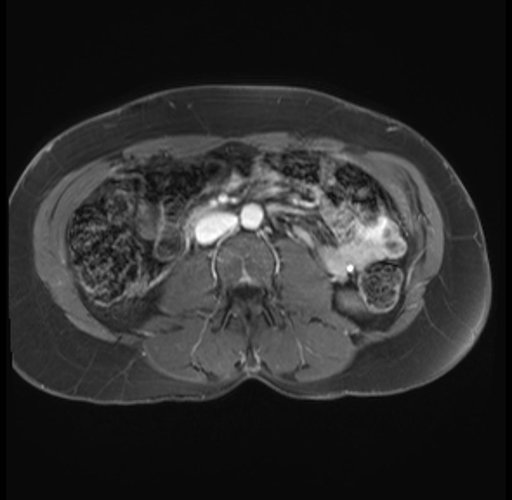

Imaging Analysis

Look through the patient's CT scan to identify any areas of concern for the necessary procedure.

Based on your CT findings, which issue(s) are present and would give reason for "planned slowing down moment(s)" in this case?